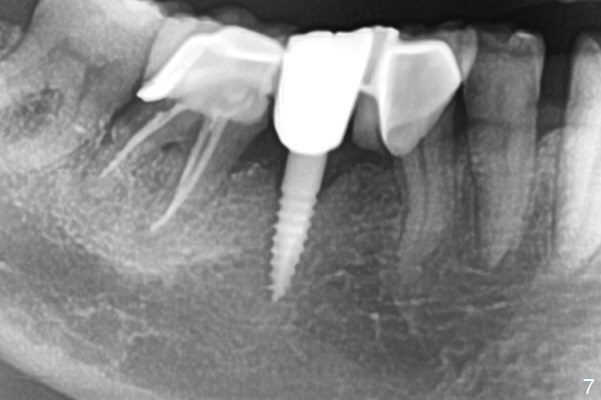

There is a space underneath the pontic at #30 (Fig.1 *), the basis for food impaction. After sectioning between the pontic and the posterior retainer, the pontic is removed from the anterior retainer with an attachment (Fig.2 *). The initial depth of osteotomy is 10 mm following ridge top reduction (Fig.3). A 3x10(4) mm 1-piece implant is placed with >50 Ncm; to reduce possibility of crown dislodgement from the implant, the retainers will be kept with modification of the proximal surfaces as shown by curved lines in Fig.4. Periodontal dressing is applied after suturing. There is no postop paresthesia. The periodontal dressing remains in place 2 weeks postop because of engagement into the attachment slot and undercuts (Fig.5). The patient returns 3 months postop; after minor contour adjustment (Fig.6 red curved line), impression is taken. The permanent crown is temporarily cemented (3.5 months postop) in case of food impaction due to the distal overhang of the tooth #29 (Fig.7). In fact the patient returns 4.5 months post cementation with right TMD (muscle relaxant prescribed) and food impaction, although there is no bone resorption (Fig.8,9). It appears that the crown at #29 needs to be redone, while porcelain will be added to the mesial surface of the one at #30 (Fig.10 red lines). In fact the crown at #30 is redone because of loose proximal contact with #31; there is no bone resorption 13 months post cementation (Fig.11). Bone resorption remains unnoticeable 28 months post cementation (Fig.12,13).